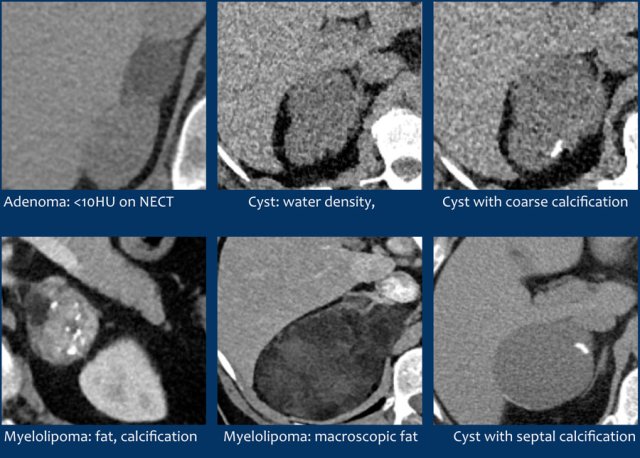

Here some examples of typically benign lesions.

Lipid-rich adenoma

70% of adenomas contain high intracellular fat and will be of low attenuation on unenhanced CT [4,5].

A density equal to or below 10 HU is considered diagnostic of a lipid-rich adenomas.

Using a safe threshold value of 10HU on a native CT scan results in a sensitivity of 70-79% and a high specificity of 96-98% for the diagnosis of an adenoma [5-7].

Cyst

An uncomplicated cyst is a well-defined lesion of water density that does not enhance.

A cyst has a thin wall and may have thin septa.

It may be an endothelial cyst or a pseudocyst, which are the most common, or a true epithelial or parasitic cyst (both rare) [5].

Pseudocysts may have thicker walls.

Hemorrhage or debris may cause increased internal attenuation.

Both benign and malignant tumors may show cystic degeneration and necrosis.

In those cases density measurements are unreliable.

Features of an underlying tumor may be an irregular thick wall of 5 mm or more and mural, septal or solid enhancement [5].

Lesions with benign calcifications Lesions with benign calcifications

Lesions with benign calcifications

Coarse rounded, peripheral or septal calcifications are typically benign and may be seen in:

• Adenoma

• Myelolipoma

• Trauma

• Granulomatous infection

Bilateral calcifications also suggest a benign origin.

Punctate, dystrophic and irregular calcifiations are not typically benign and can be seen in:

• Adrenocortical cancer

• Adrenal metastases

Myelolipoma

Myelolipomas are benign tumors composed of bone marrow elements.

Usually they are easy to recognize on CT or MR because they contain areas of macroscopic fat.

Calcifications are seen in 24% of cases.

The adrenal mass seen here on CT contains macroscopic fat, which is specific for the diagnosis myelolipoma.